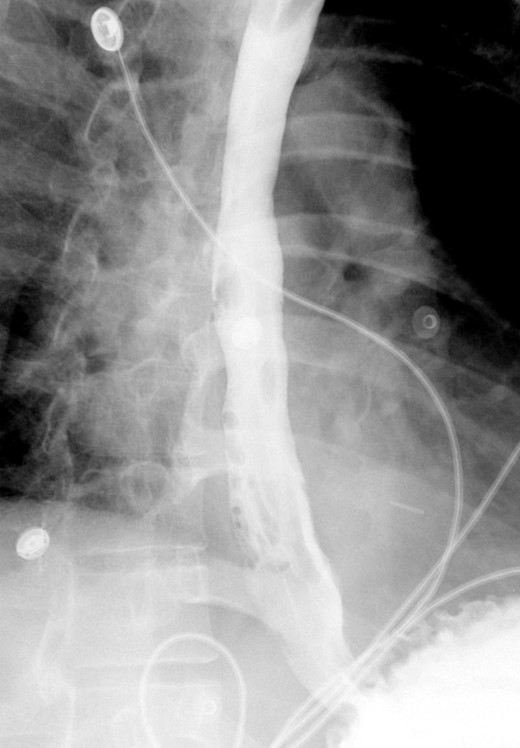

A follow-up EGD was performed 6-weeks later for stent removal. Although the stent had migrated slightly, it continued to cover the previous perforation site. The stent was removed, and the esophagus appeared well healed with no residual tear. Contrast study showed no residual leak or significant stricture (Fig. 4). On follow-up endoscopy, biopsies from the proximal and distal esophagus revealed 20 eos/hpf and 30 eos/hpf, respectively. The patient was kept on PPI and started on topical steroids and continued to do well with no reported symptoms on the last follow up 9 months and two years and a half after the initial presentation.

Shows interval removal of the esophageal stent with no evidence of an esophageal leak.